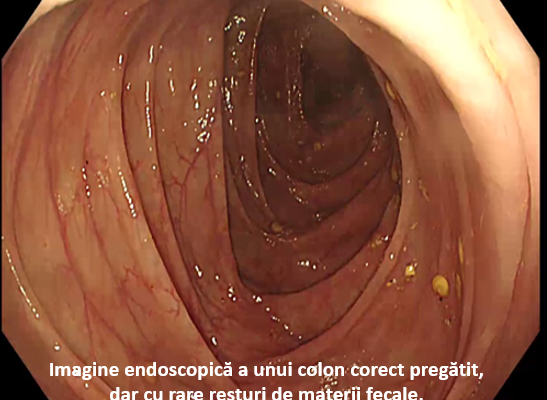

Colonoscopia este o investigație care necesită o anumită pregătire anterioară a pacientului, astfel încât să poată fi examinat corect întregul colon. Criteriile pe care trebuie să le întrunească o colonoscopie pentru a fi catalogată de înaltă calitate sunt: - evaluarea...